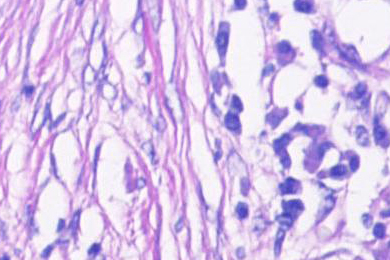

Lunge, aufgenommen im Hellfeld